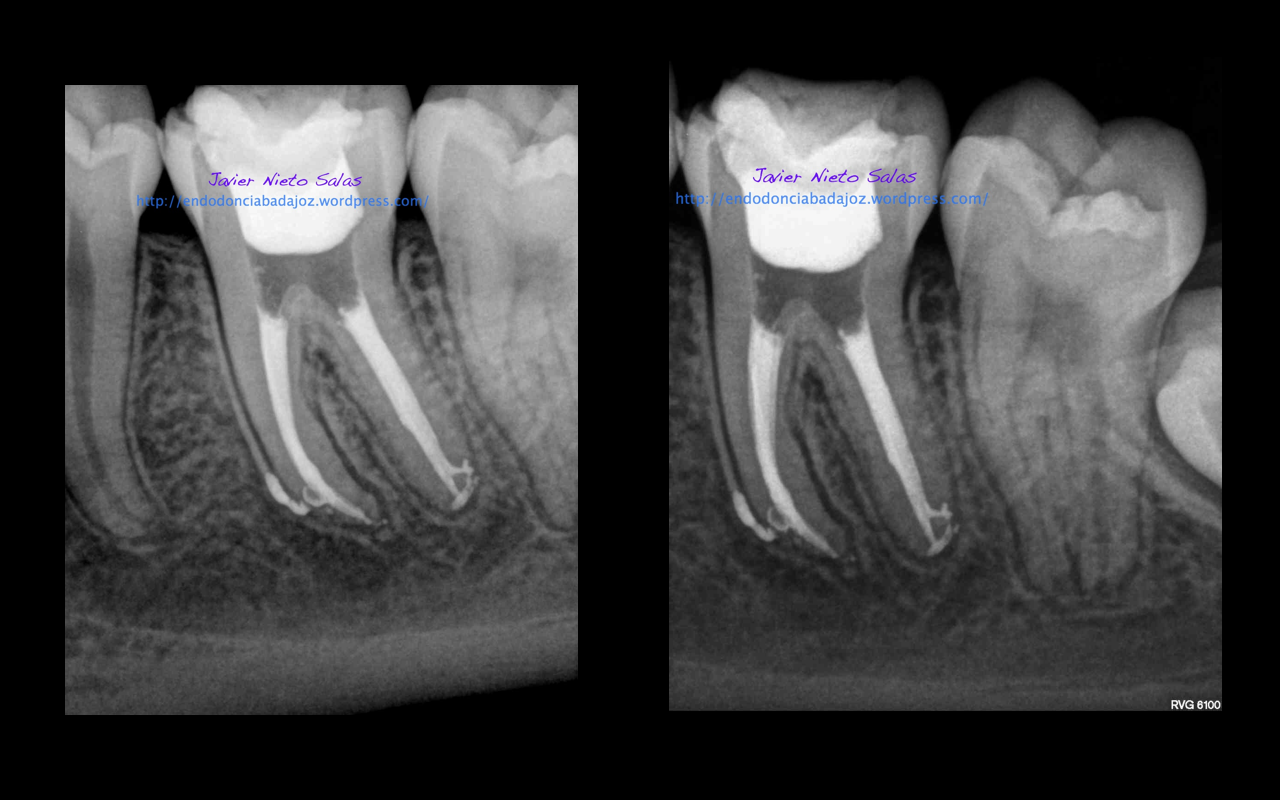

Se trata de un par de molares inferiores con lesiones apicales (Periodontitis apicales crónicas ). Consecuencia de caries profundas en su momento.

Se tratan del caso A y el caso B, por orden de posición, ambos casos se instrumentaron de la misma manera, elegimos Protaper hasta una F2, ambos casos se realizaron en una sesión tras abundante irrigación y finalmente se obturaron con condensación Vertical con la técnica de Ola continua de Buchanan complementando en el backfilling con guatpercha inyectada con la Pistola Obtura II.

Caso A:

Llamamos a la paciente a revisión a los 10 meses: